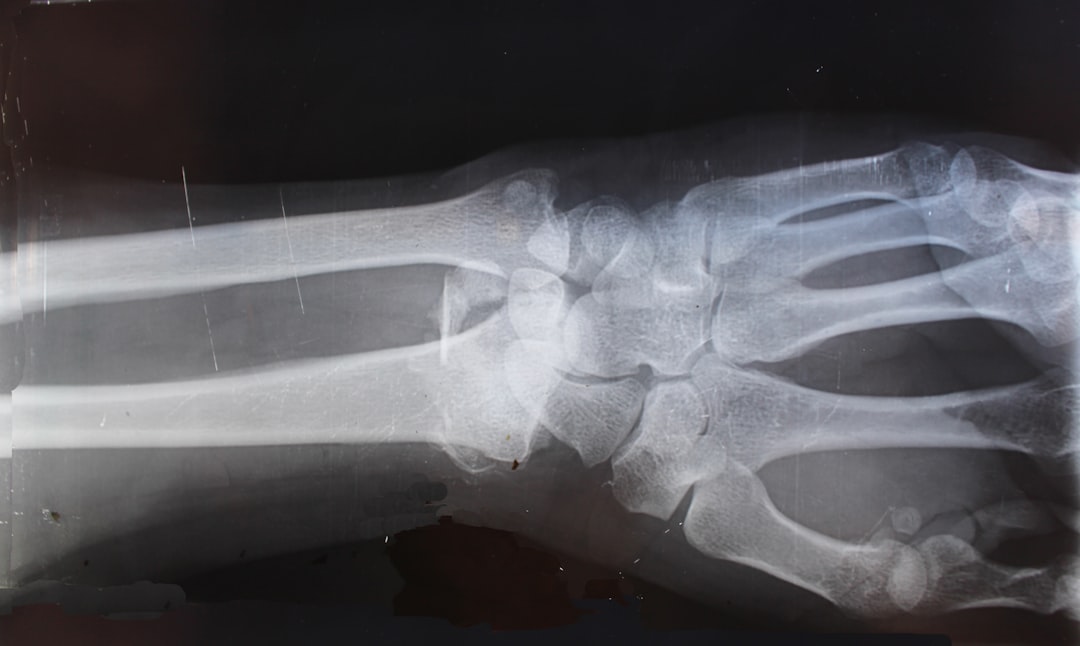

손가락 관절염은 의사의 진찰과 함께 X선 검사, 혈액 검사 등을 통해 진단할 수 있습니다.